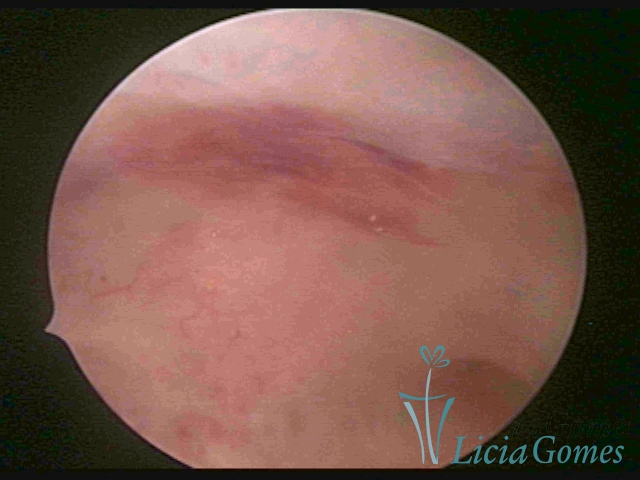

On Advanced chronic endometritis, a thin endometrium is observed, presenting denude, sometimes ulcered areas of a greenish gray color with micro varicosities presenting a hazel color, more accentuated in the cornual regions (vascular dystrophy.)